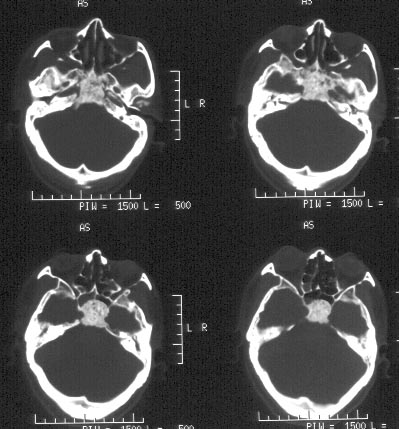

男性,48岁。吸涕带血2月余。

ct平扫:鼻咽腔明显狭窄,鼻咽顶壁、顶后壁、后壁、双侧壁增厚,右侧甚,右侧鼻咽旁间隙、颈动脉间隙见软组织肿物占据,肿物向前达后鼻孔,向下达右侧口咽,肿物向中颅窝侵犯致广泛颅底骨质破坏:包括枕骨斜坡、枕大孔、蝶窦、鞍底、双侧蝶骨大翼、双侧岩尖、双侧翼板。蝶窦、蝶鞍为软组织肿物占据,左侧海绵窦稍增厚。左侧鼻咽旁间隙、颈动脉间隙未见明显异常。

ct诊断:考虑鼻咽癌,并口咽受侵犯、颅底骨质破坏。